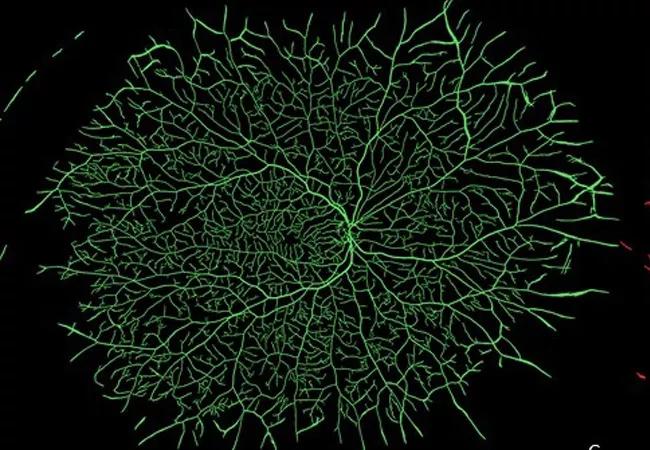

Ultra-widefield fluorescein angiograms of an eye with minimal retinal pathology (A) and an eye with early proliferative diabetic retinopathy (B) and their corresponding vessel segmentations (C, D). Eye with minimal pathology demonstrates generally uniform vascular distribution (green), while eye with advanced diabetic eye disease demonstrates both multiple areas of capillary dropout and localized increased density/tortuosity (red).